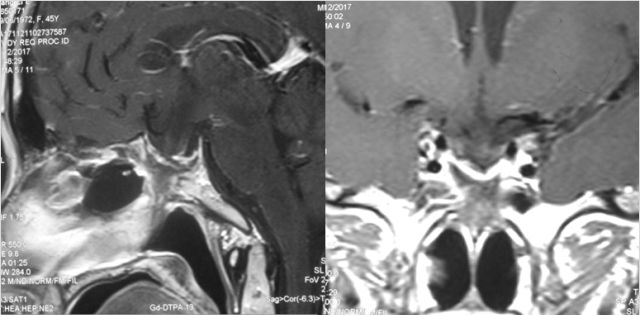

听神经瘤

手术体位个性化选择

术前

术后